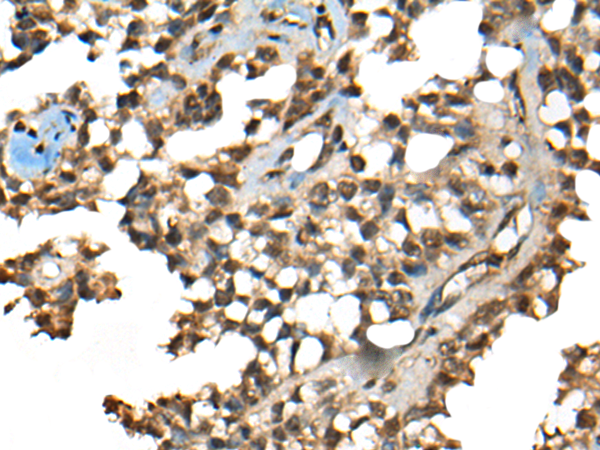

IHC (Immunohiostchemistry)

(The image on the left is immunohistochemistry of paraffin-embedded Human ovarian cancer tissue using 46418(CCDC12 Antibody) at dilution 1/60, on the right is treated with fusion protein. (Original magnification: x200))